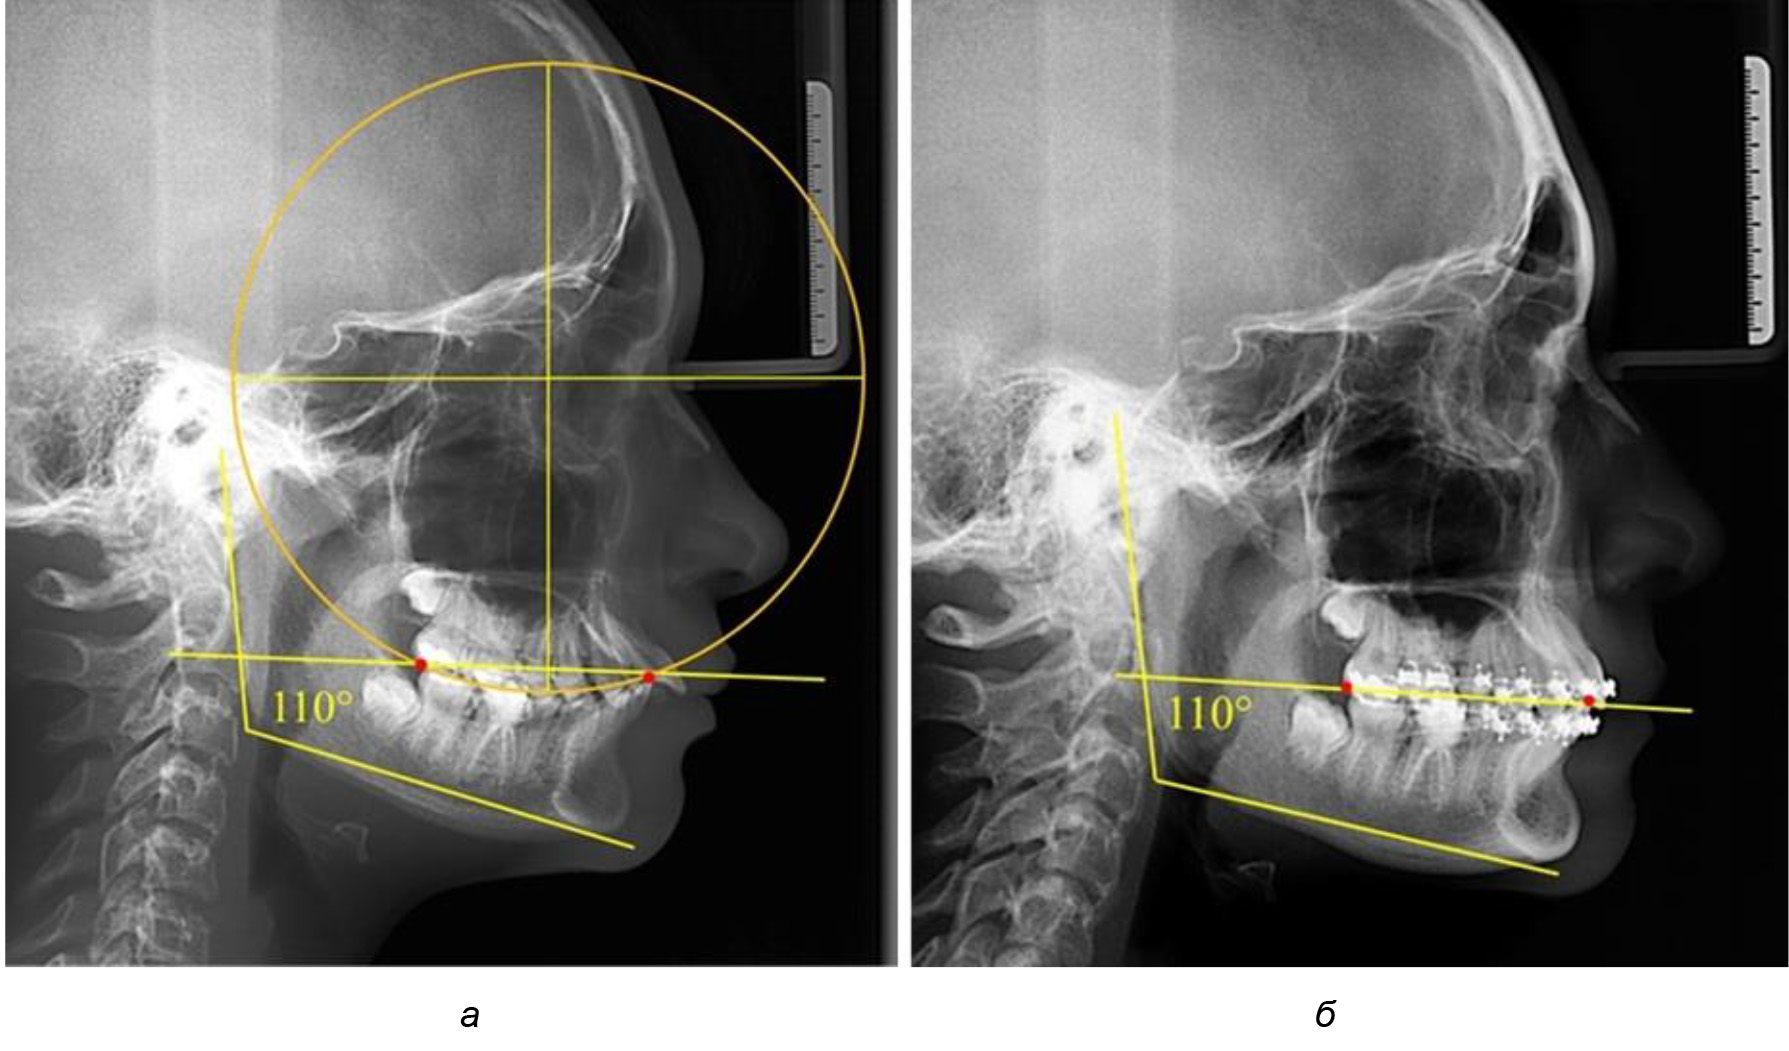

На рентгенограммах людей 2-й подгруппы (30 человек с нейтральным типом роста) величина угла нижней челюсти в среднем составила (120,34 ± 2,19) ° и характеризовала нейтральный тип нижней челюсти.

Глубина кривой Spee в среднем по 2-й подгруппе составил (3,54 ± 0,58) мм, что было незначительно меньше, чем при анализе аналогичного показателя 1-й подгруппы.

Достоверных различий с показателями, полученными при анализе ТРГ и ОПТГ, нами не отмечено (р ˃ 0,05). Деление величины радиуса круга к длине окклюзионной линии составило 1,612 ± 0,02, что, так же как и в 1-й подгруппе, было близким по значению к числу Фибоначчи (1, 618).

В 3-ю подгруппу вошли ТРГ и ОПТГ 14 человек 1-й группы, что составило (22,58 ± 5,31) % от общего количества людей 1-й группы. Величина угла нижней челюсти в среднем составила (114,85 ± 2,87)° и характеризовала горизонтальный тип нижней челюсти.

Глубина кривой Spee в среднем по 2-й подгруппе составил (2,94 ± 0,47) мм, что было меньше, чем в других подгруппах. Деление величины радиуса круга к длине окклюзионной линии составило 1,616 ± 0,02 (рис. 4).

Рис. 3. Особенности кривой Spee на ТРГ (а) и ОПТГ (б) при нейтральном типе роста нижней челюсти

Рис. 4. Особенности кривой Spee на ТРГ (а) и ОПТГ (б) у людей с горизонтальным типом лица